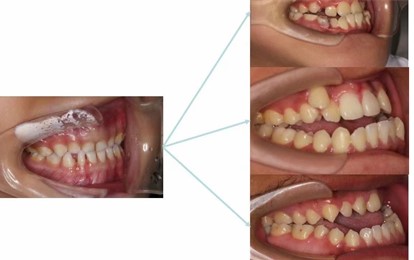

吴博士提供了自己一个5岁和一个9岁的孩子的早期矫正临床案例,并建议我们地包天的矫正时间是3-5岁,切记不要等到12岁再看,不然容易出现严重的咬合和脸型问题。如果家长无法判断咬合是否有问题,孩子3岁可以做第一次的正畸专科检查,防范于未然。

5岁男孩,通过4个月的早期矫正干预,

下唇外翻解决,脸型明显的改善。

9岁女孩通过早期矫正干预,

下颌前突解决,脸型变好。